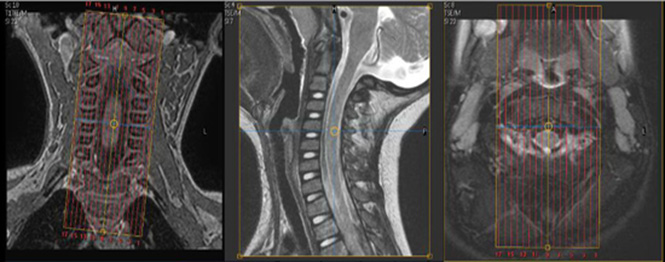

- Coil: NV and Anterior Torso Coil

| Plane | Weighting | Mode | Slice (mm) | Gap (mm) | FAT SAT | FOV (cm) | MPR (mm) | Notes |

|---|---|---|---|---|---|---|---|---|

| SAG | T2 | 3D TSE | 1 or less | 0 or less | no | AXIAL 1/0 | ||

| SAG | T2 | 2D TSE dixon | 3 | 0 | Dixon: InPhase & Water only | no | ||

| SAG | T1 FLAIR | 2D IR-TSE | 3 | 0 | no | no | ||